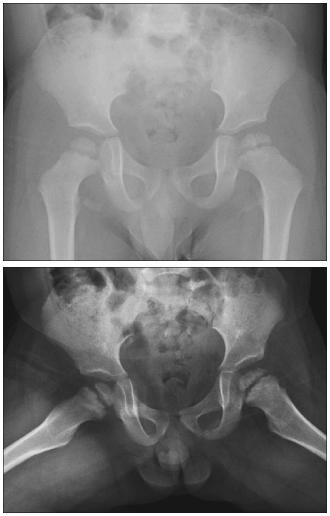

Bone scans are normal in Meyer dysplasia. MRI scans show multiple centers of ossification of the femoral head with normal signal intensities in all sequences; these findings are suggestive of homogenous vascularization of epiphyseal cancellous bone, articular cartilage, physis, and cortical bone. Reduced height of the cartilaginous epiphysis may also be observed.

This patient’s radiographs showed cortical irregularity and sclerosis of the left femoral head, without effusion or dislocation (Figure 1). Because these findings may also represent Legg-Calvé-Perthes disease, MRI was performed to confirm the diagnosis of Meyer dysplasia (Figure 2).

Concurrent Meyer dysplasia and Legg-Calvé-Perthes disease may complicate diagnosis. Differentiation between the 2 conditions can be aided by the appearance of a subchondral fracture line, increased density of epiphysis, and lateral displacement of the femoral head. These are early characteristics present only in Legg-Calvé-Perthes disease. MRI can help differentiate Meyer dysplasia from the early fragmentation stage of Legg-Calvé-Perthes disease.